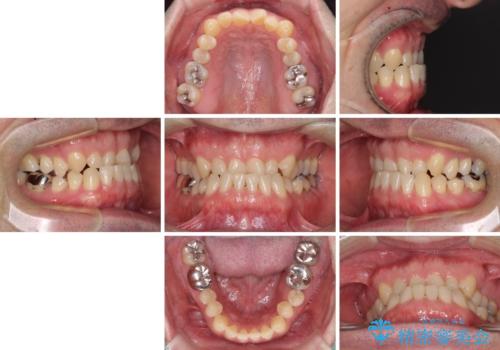

- 上下前歯の反対咬合と左下奥歯の痛みを気にして来院された患者様です。

歯並びや口元の印象、奥歯の咬み合わせから、非抜歯にて矯正治療を行うこととしました。

また、左下の奥歯は親知らずの影響で手前の歯の歯根までむし歯になってしまったため、親知らずとともに抜歯をし、インプラントによる補綴治療を行うこととしました。

インプラント埋入による仮歯の装着や、前歯の反対咬合の改善は比較的スムーズに達成されましたが、舌突出癖などの影響による、歯列全体のスペースを閉じることが難航し、期間がかかってしまいました。